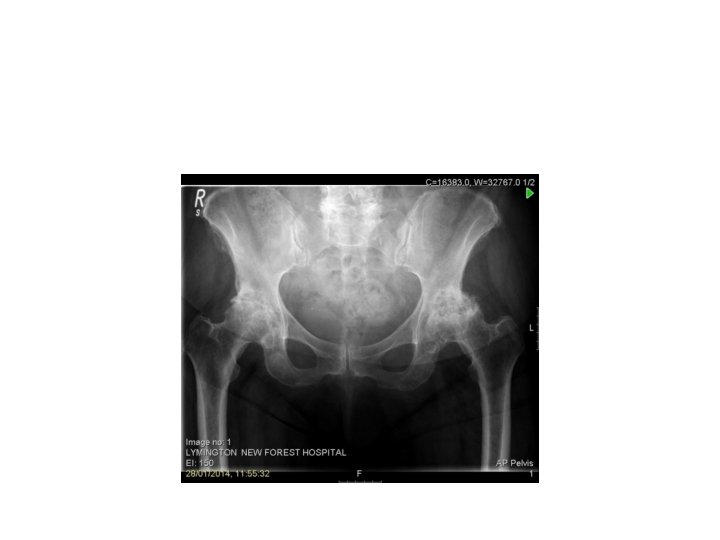

Hip • • OA Bursitis Labral Tear Dysplasia

OA • • • Groin Buttock Anterior thigh pain – referral pattern Loss of rotation Putting shoes on/etc

Bursitis • Lateral or posterior thigh pain • Biomechanical • Worse at night and after sitting • Rest, ICE etc • Can be injected

• • Labral Tear Catching/after actvity Younger/sporting FABER/FADIR/Scoop • Modify activity • X-ray – Cam/Pincer lesion/impingement • Ortho Consultant opinion